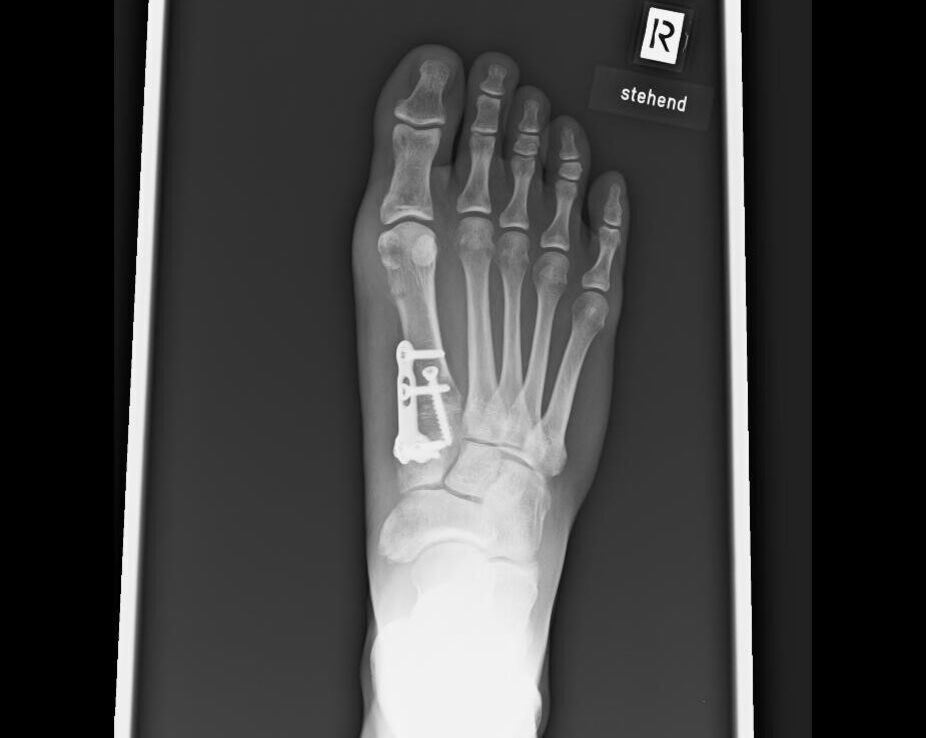

Ergänzend zur Untersuchung sollte ein Röntgenbild des ganzen Fußes unter Belastung in zwei Ebenen angefertigt werden. Spezielle Winkelmessungen ermöglichen die Bestimmung des Schweregrades der Fehlstellung. Zeichen des Gelenkverschleißes werden sichtbar und können bei der Erstellung des Therapiekonzeptes berücksichtigt werden.

Die Lapidusarthrodese

Bei höhergradigen Fehlstellungen liegt häufig eine Instabilität des 1. Fußwurzelgelenkes vor. In diesen Fällen wird die Fehlstellung durch eine Fußwurzelversteifung korrigiert.

Zunächst werden die gelenkumgebenden Weichteile gelockert und der knöcherne Vorsprung des 1. Mittelfußknochens abgetragen. Nach Darstellung des 1. Mittelfußgelenkes wird der Gelenkknorpel entfernt und der Knochen angefrischt. In korrigierter Stellung erfolgt die Fixierung mit einer Platte und Schrauben.

Nach Entfernung der Fäden ist in einem Spezialschuh eine Teilbelastung mit 20 kg an Unterarmstützen für weitere vier Wochen erlaubt. Nach sechs Wochen wird ein Röntgenbild angefertigt. Ist der Knochen verheilt, kann der Fuß in normalem Schuhwerk voll belastet werden.